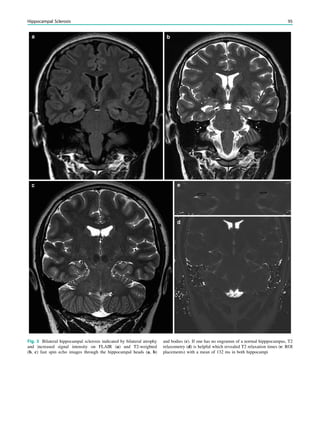

4.2 Spatial Resolution.................................................................. 32

4.3 Contrast.................................................................................. 33

4.4 Contrast Medium Injection ................................................... 34

5 MRI Interpretation.............................................................. 34

6 MRI Protocols...................................................................... 34

References...................................................................................... 35